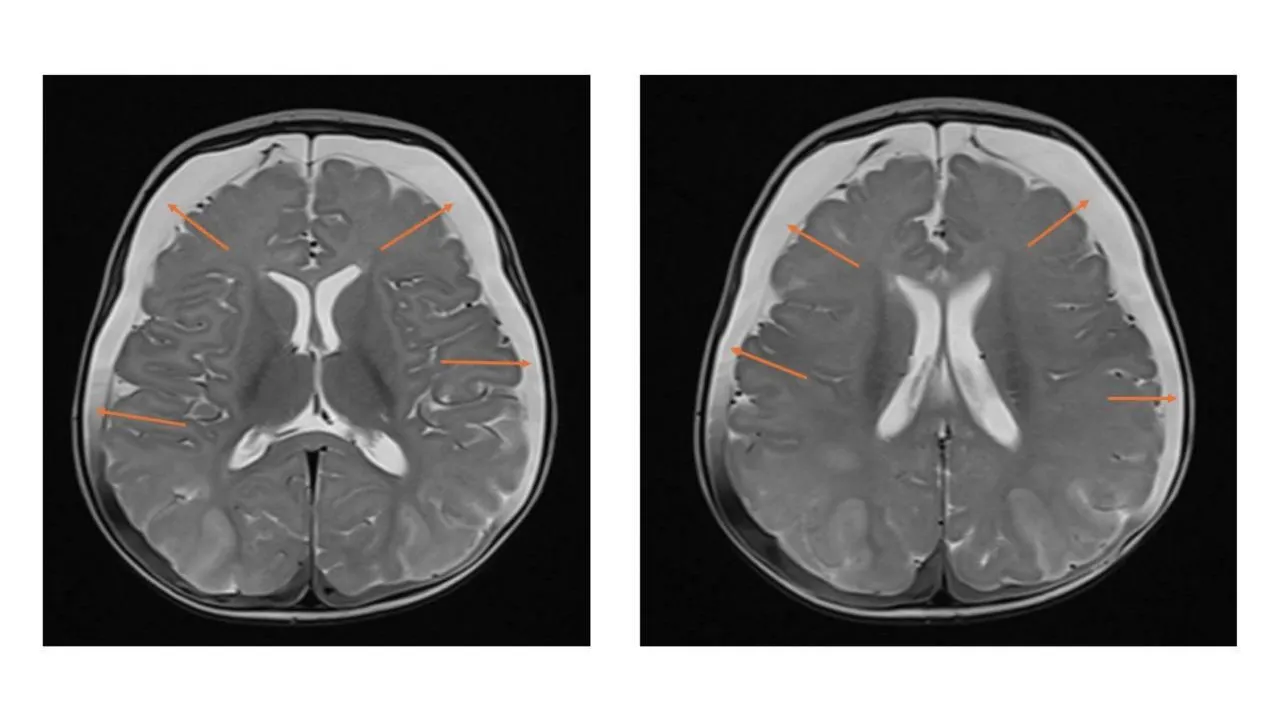

МРТ выявило у ребенка следы перенесенных кровоизлияний и признаки серьезного нарушения кровоснабжения. В результате врачи поставили диагноз — ННН-синдром. Это редкое генетическое заболевание, при котором организм не может перерабатывать белок, в результате чего происходит отравление аммиаком, разрушающее мозг.